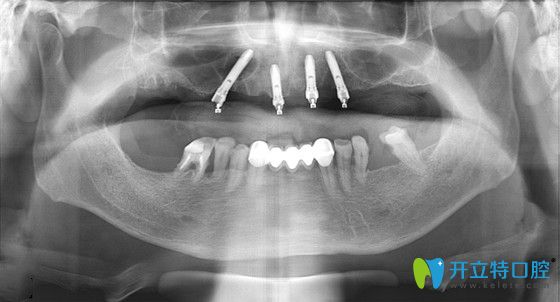

鉑爾口腔的種植醫(yī)生吳爽杰院長,從張大爺?shù)呐钠瑱z查中了解到,雖然張大爺?shù)难例X缺失多年,但牙槽骨條件還算可以,比較適合做種植牙修復。因為,張大爺?shù)娜谘例X幾乎全部都缺失了,為了減少種植手術的痛苦、降低費用,吳院長建議張大爺做ALL-ON-4即刻負重的種植技術。

張大爺即刻負重手術過程全記錄:首先,吳院長運用了三維數(shù)字軟件,精準的測量了張大爺?shù)难啦酃敲芏?、高度、寬度等信息,確定了種植位置,經(jīng)過1個多小時,復雜而有序的專業(yè)操作后,完成了種植體的種植操作;然后又為張大爺安裝了基臺、牙冠;當天回到家就能吃東西啦!

ALL-ON-4即刻負重技術,只用4--6顆種植體就能恢復半口牙的咀嚼功能▼